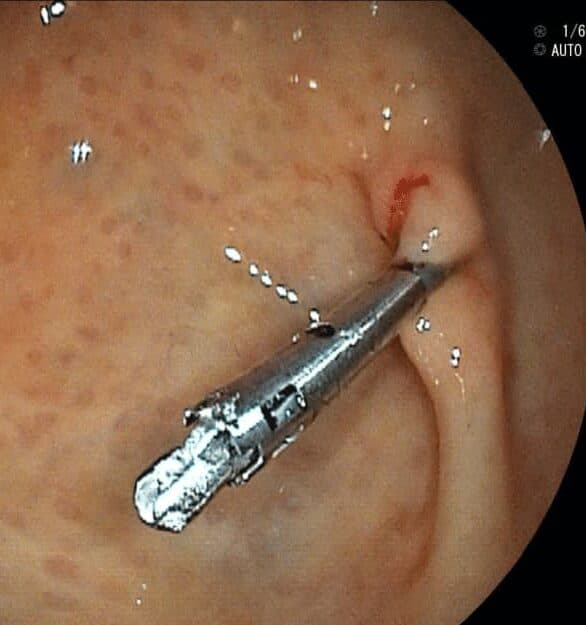

Clip Hemostático

Dispositivo para cerrar vasos sanguíneos y detener hemorragias.